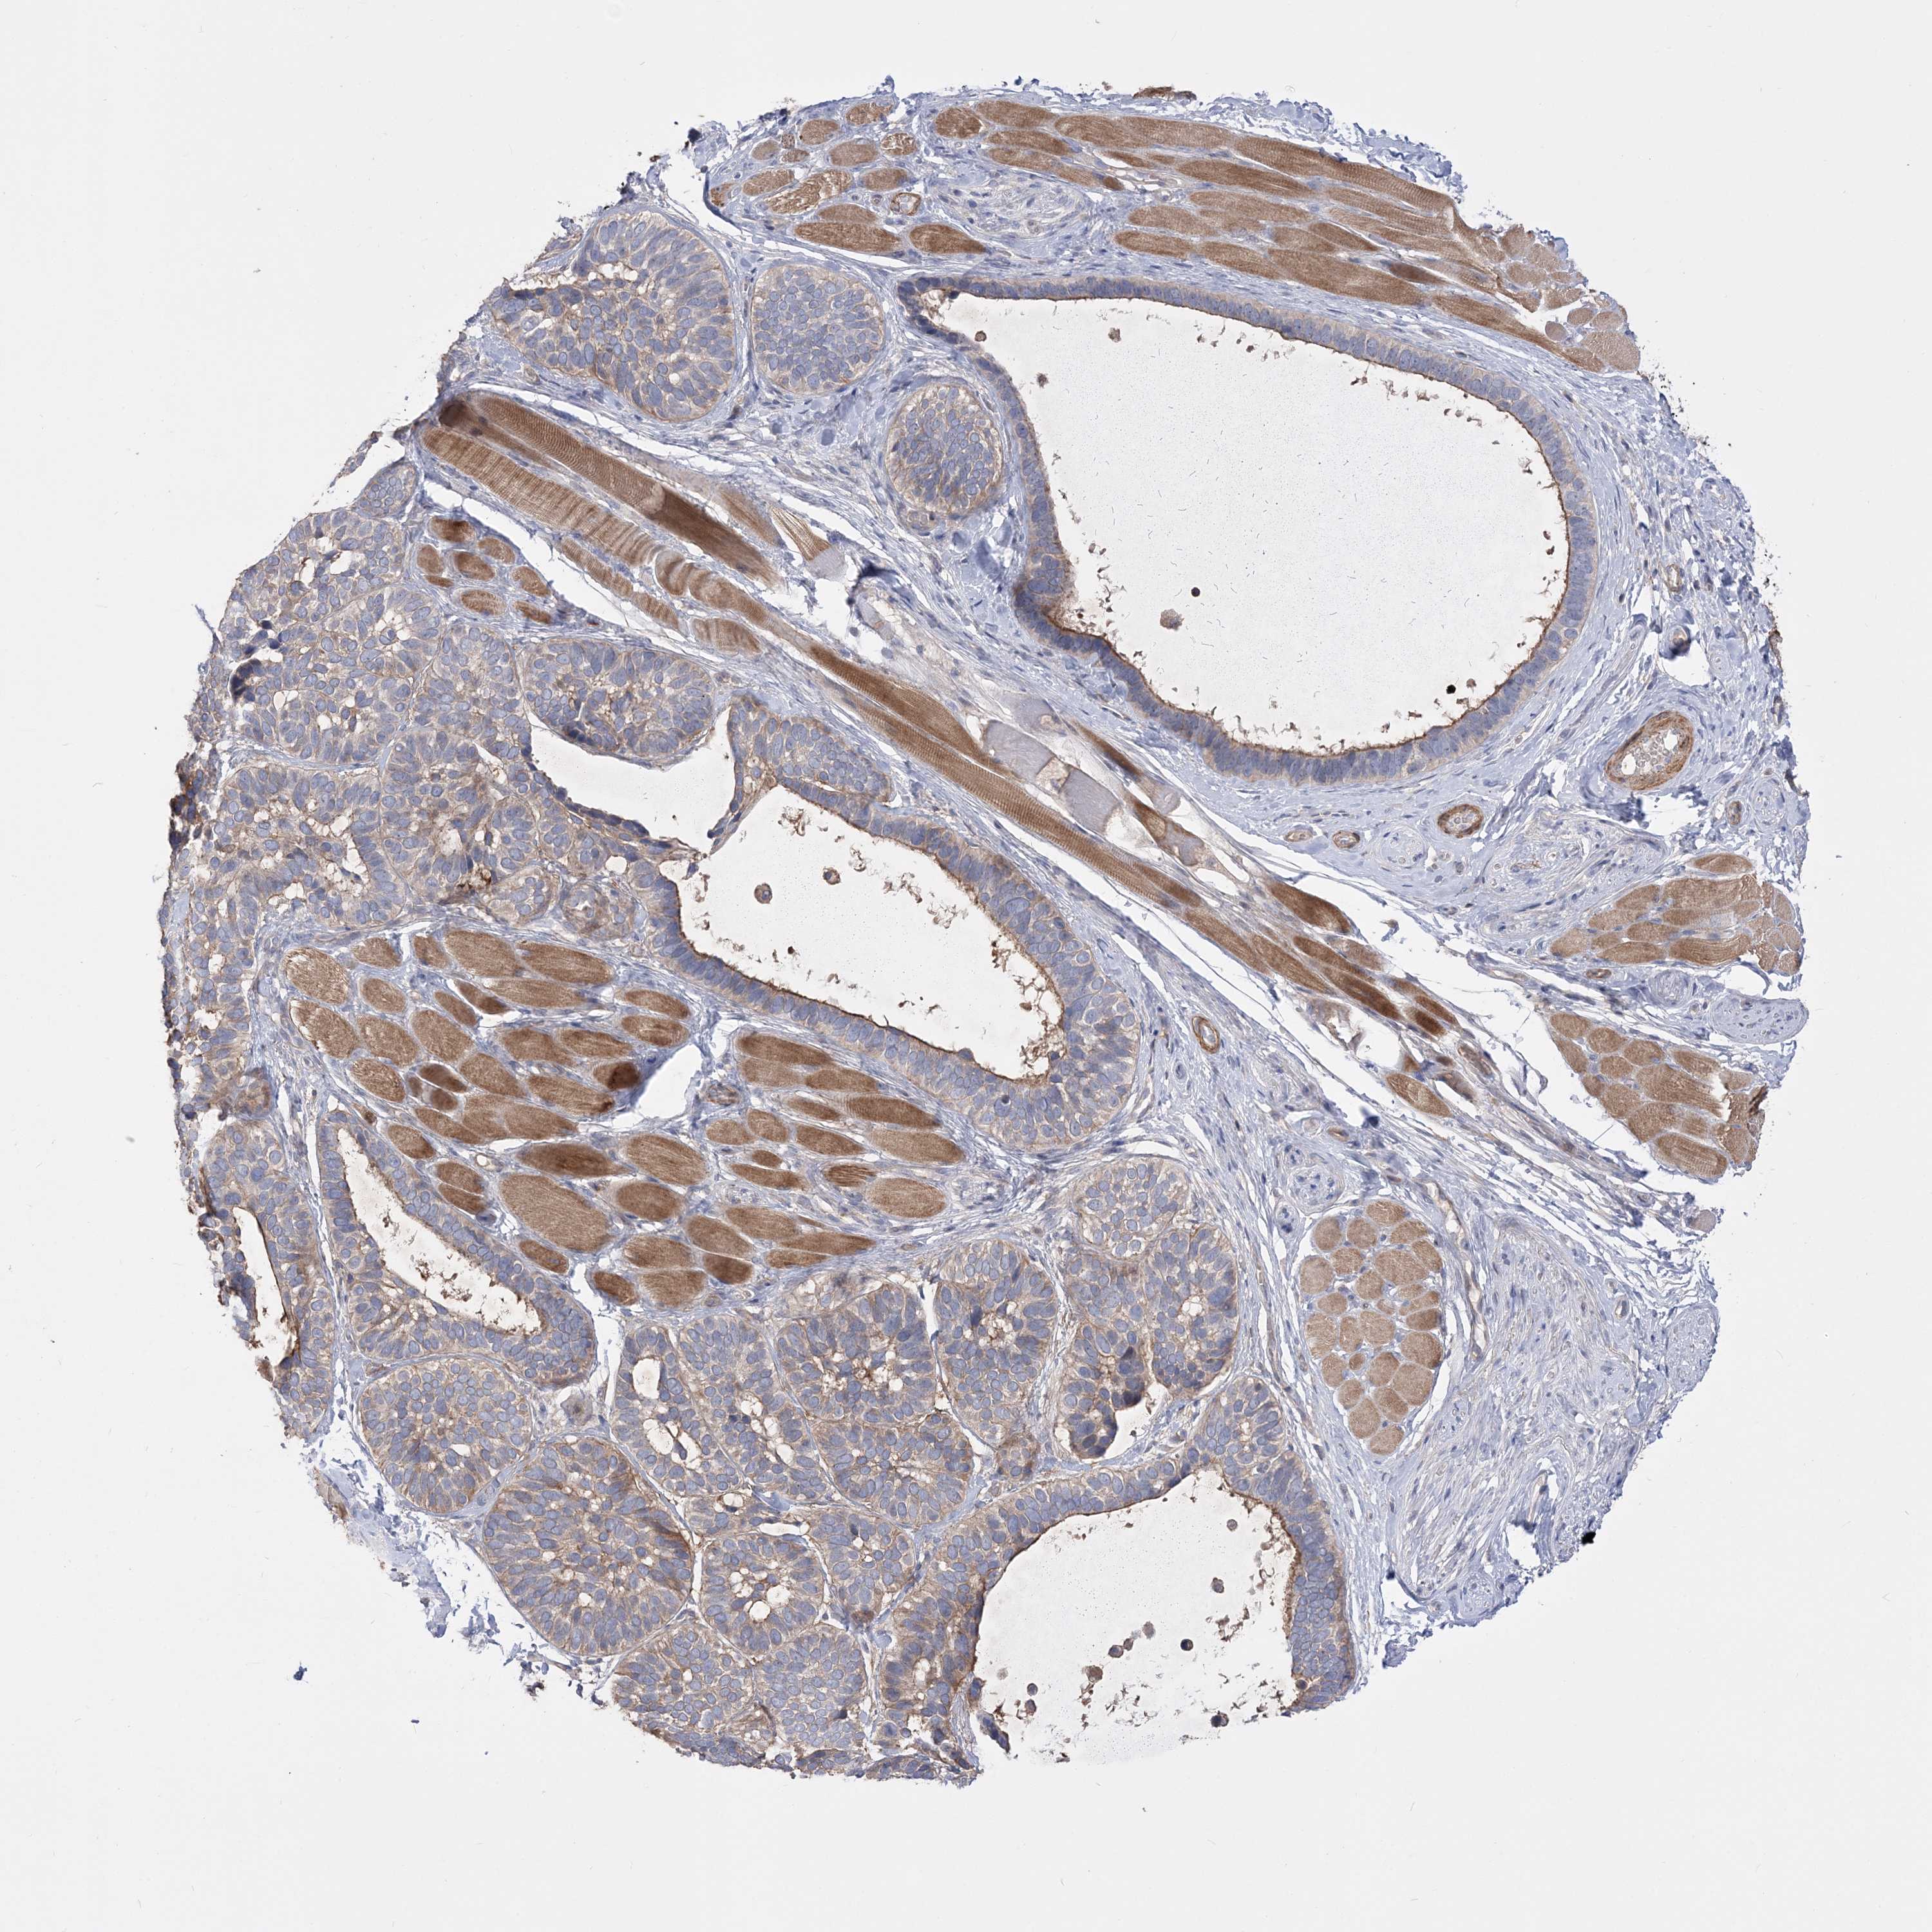

SKIN CANCER - Protein expressioni

A mouse-over function shows sample information and annotation data. Click on an image to view it in a full screen mode. Samples can be filtered based on level of antibody staining by selecting one or several of the following categories: high, medium, low and not detected. The assay and annotation is described here.

Antibody stainingi

Antibody staining in the annotated cell types in the current human tissue is reported as not detected, low, medium, or high, based on conventional immunohistochemistry profiling in selected tissues. This score is based on the combination of the staining intensity and fraction of stained cells.

Each image is clickable and will lead to virtual microscopy that enables deeper exploration of all samples and also displays staining intensity scores, fraction scores and subcellular localization as well as patient and tissue information for each sample.

Antibody HPA022994

Antibody HPA023065

Squamous cell carcinoma, NOS

Squamous cell carcinoma, metastatic, NOS